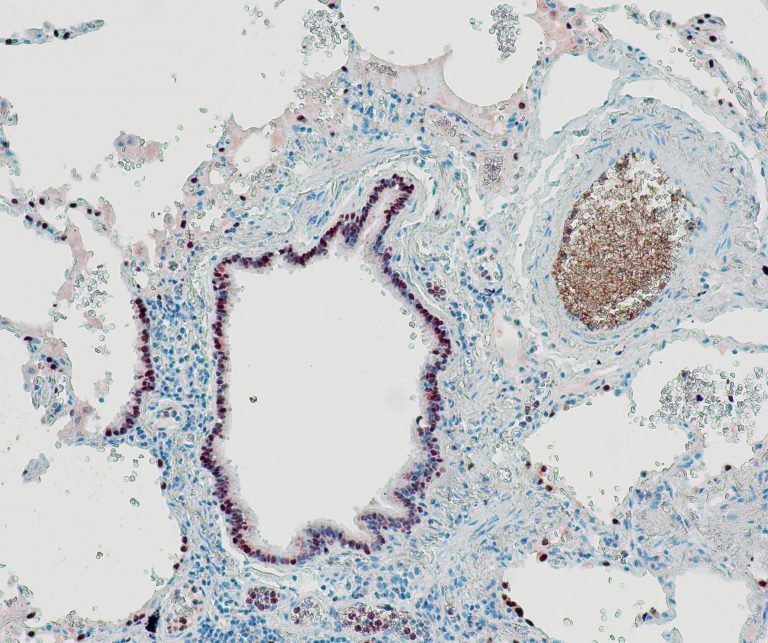

Vascular Pathology

Lung Pathology

Urinary Tract Pathology